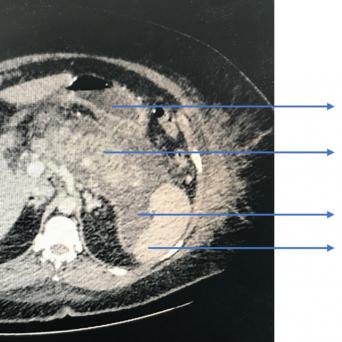

L’image

du jour

Illustration.